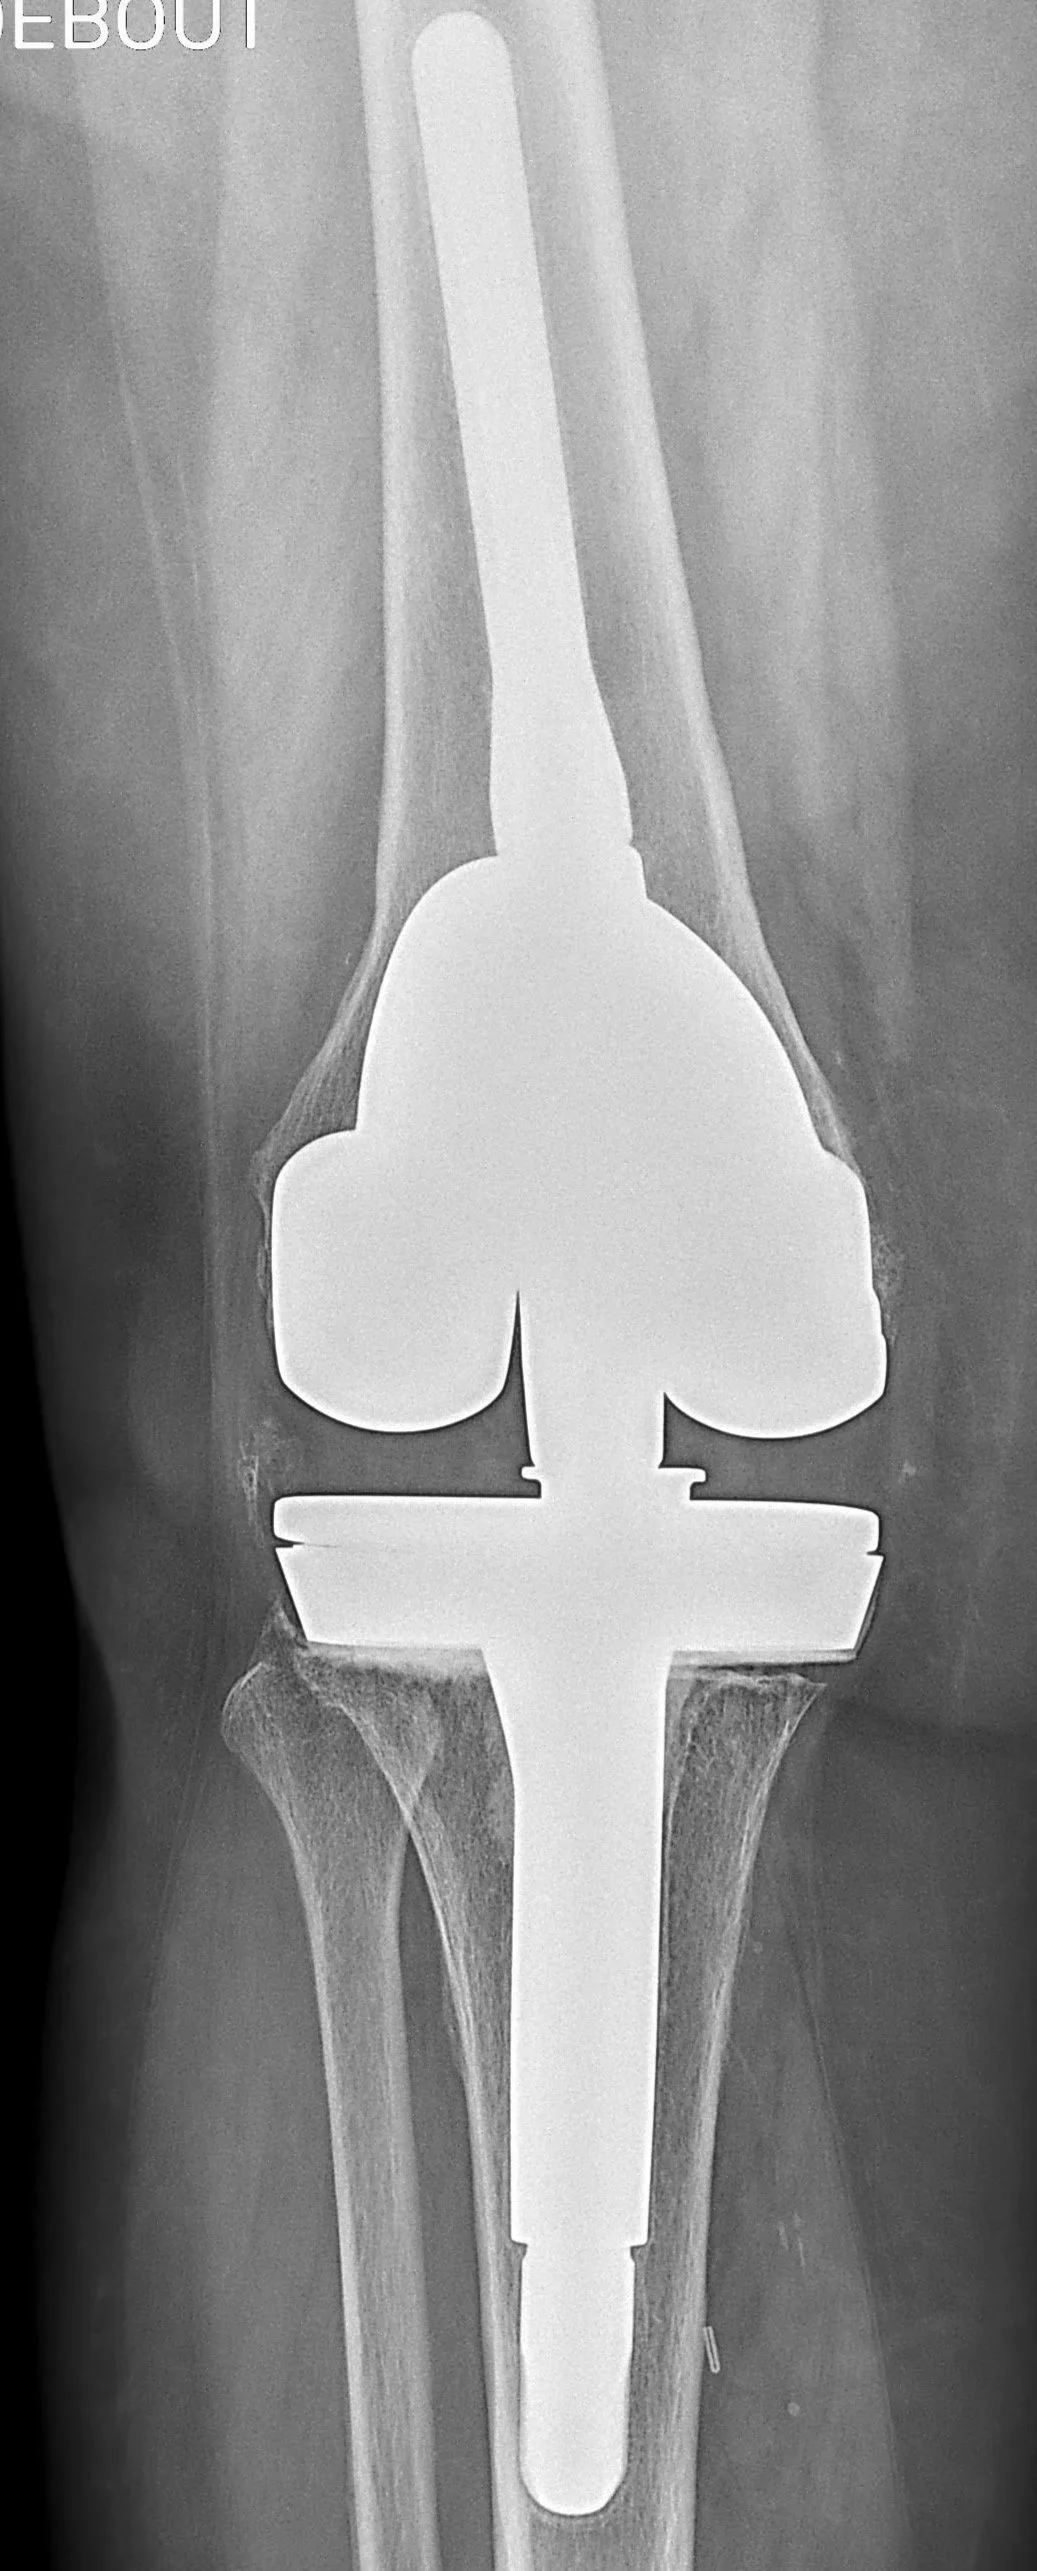

- Examens radiologiques : - radiographies : présence d’un liseré c’est à dire un espace entre l’os et la prothèse comme sur la photo en haut de l’article,